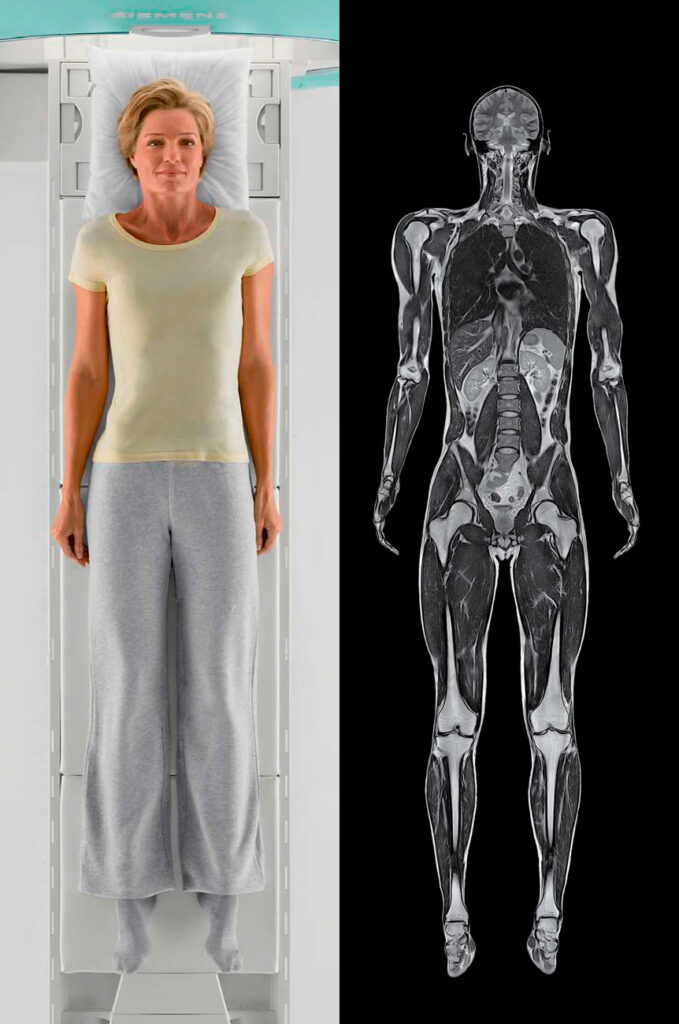

Magnetic Resonance Imaging is a medical imaging technique that uses strong magnetic fields and radio waves to create detailed images of the inside of the body. MRI provides valuable information about the structure and function of organs, tissues, and various parts of the body, making it a powerful tool for diagnosing and monitoring a wide range of medical conditions.

MRI is a versatile imaging technique that can be used to examine various parts of the body, including the brain, spine, joints, abdomen, and pelvis.

It is particularly useful for visualizing soft tissues like organs, muscles, tendons, ligaments, and the central nervous system. Unlike X-rays or CT scans, MRI does not use ionizing radiation, making it a safer option for many patients, including pregnant women and children. MRI is a valuable tool in modern medicine, providing non-invasive and detailed imaging that helps healthcare professionals make accurate diagnoses and develop effective treatment plans for patients.